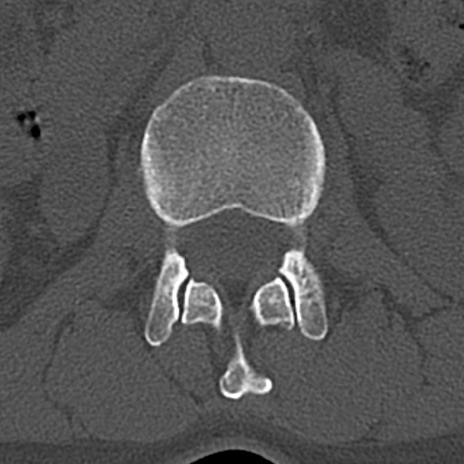

腰椎CT

横断像と矢状断像